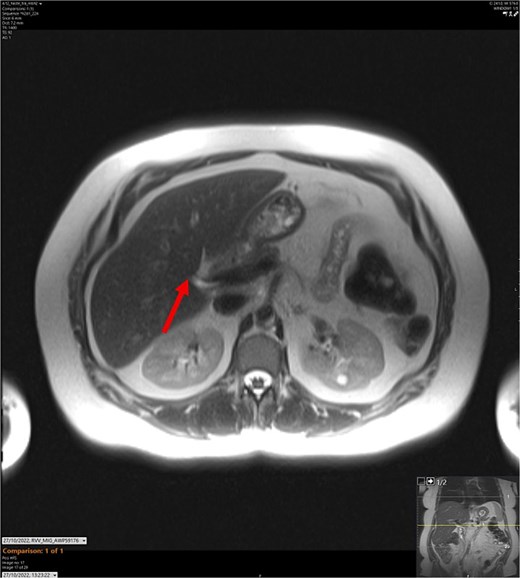

On admission, the patient’s blood tests showed normal inflammatory markers, liver function markers, and amylase (Table 1). The patient underwent an abdominal ultrasound scan, which did not visualize gallstones or the gallbladder. A computerised tomography (CT) abdomen-pelvis scan was done, and the gallbladder could not be visualized (Figs 1 and 2). Further investigations, which include a magnetic resonance cholangiopancreatography (MRCP) and hepatobiliary iminodiacetic acid (HIDA) scan, confirmed a gallbladder bud with an intact biliary tree (Figs 3–6). The patient denied a history of a cholecystectomy. She was diagnosed with gallbladder agenesis.

T2-weighted MRCP scan in axial view. The arrow points to where we expect the gallbladder to be seen, but it cannot be visualized on the scan.